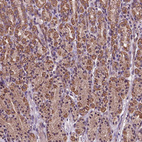

Immunohistochemical staining of human stomach shows cytoplasmic positivity in subset of glandular cells.